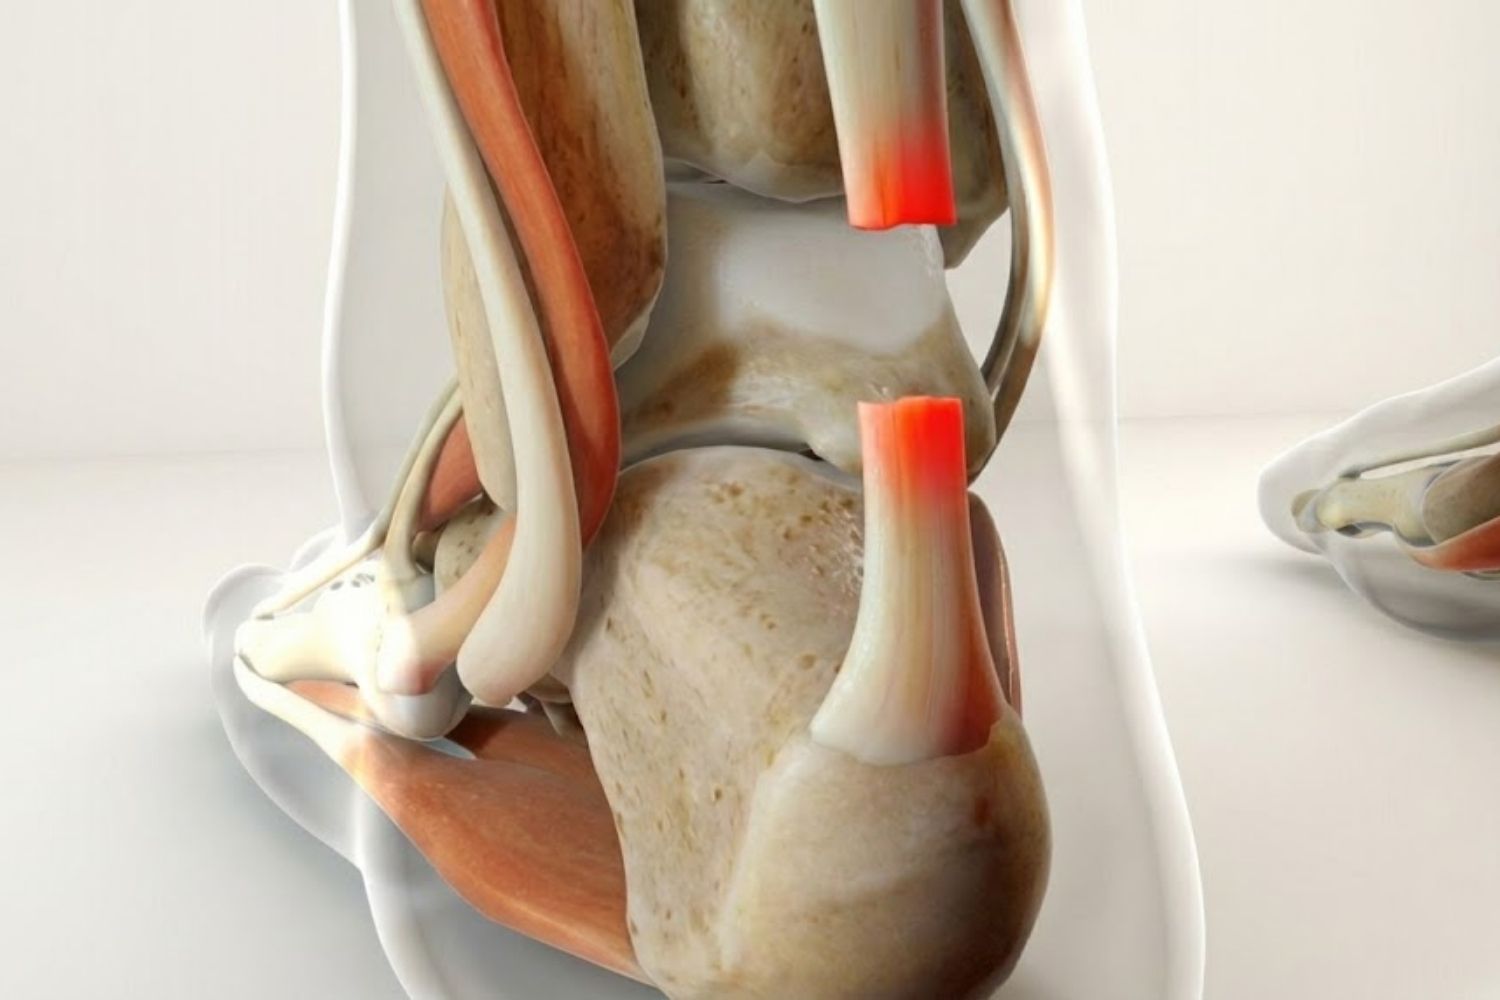

Cirugía de ligamentos

Cirugía de ligamentos (ej. rodilla)

Reparación o reconstrucción de ligamentos cruzados y laterales dañados.

Cirugía de meniscos

Sutura o remodelación del tejido meniscal lesionado para preservar la articulación.